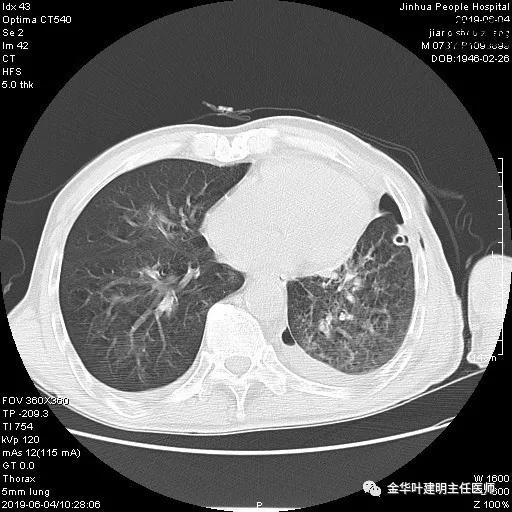

考虑左侧大量胸腔积液,遂进一步胸部CT检查:

以上是肺窗表现,下面为纵隔窗影像: